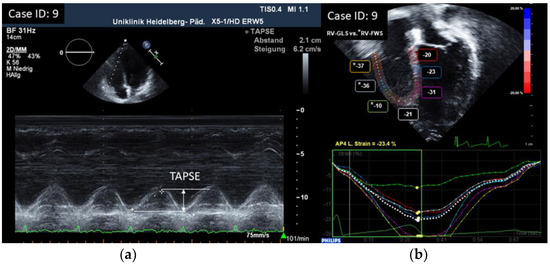

| (a) | |||||||

| ID | TAPSE cm | RV GLS % (ped.) | RV FWS % (adult) | TV S’ Vmaxcm/s | RV FAC % | RV-MPI | |

| 1 | 1.9 | −22.6 | / | 12.6 | 44.5 | 0.24 | |

| 2 | 1.7 | −25 | / | 12.1 | 43.1 | 0.23 | |

| 3 | 1.9 | −16.5 | / | 11.2 | 41.4 | 0.32 | |

| 4 | 2.7 | −11.6 | / | 12.4 | 48.6 | 0.31 | |

| 5 | 1.8 | −24.1 | / | 11.4 | 40.5 | 0.21 | |

| 6 | 1.8 | / | −23.3 | 11.5 | 43.0 | 0.38 | |

| 7 | 2 | −23.4 | / | 11.5 | 41.2 | 0.21 | |

| 8 | 1.9 | −22.9 | / | 15.3 | 40.6 | 0.21 | |

| 9 | 2.1 | / | −27.7 | 14.5 | 42.2 | 0.29 | |

| 10 | 1.9 | −20.9 | / | 17.5 | 49.0 | 0.36 | |

| 11 | 1.9 | −21 | / | 22.9 | 42.9 | 0.35 | |

| 12 | 2 | / | −22.7 | 13.2 | 42.3 | 0.27 | |

| 13 | 2 | / | −22.3 | 10.4 | 39.3 | 0.43 | |

| 14 | 1.5 | −23.6 | / | 8.44 | 47.0 | 0.33 | |

| 15 | 1.7 | / | −22.3 | 8.4 | 37.4 | 0.21 | |

| 16 | 2.3 | / | −28.0 | 14.3 | 40.2 | 0.26 | |

| 17 | 2.14 | −25.2 | / | 13.7 | 40.5 | 0.28 | |

| 18 | 2.1 | −22.3 | / | 9.8 | 34.0 | 0.24 | |

| Parameter | n | Mean | SD | 25% | Median | 75% | Min | Max |

|---|---|---|---|---|---|---|---|---|

| TAPSE cm | 18 | 1.96 | 0.26 | 1.83 | 1.90 | 2.08 | 1.50 | 2.70 |

| TV S’ cm/s | 18 | 12.84 | 3.41 | 11.25 | 12.25 | 14.15 | 8.40 | 22.90 |

| RV-FAC % | 18 | 42.09 | 3.68 | 40.51 | 41.80 | 43.07 | 34.00 | 49.00 |

| RV-MPI | 18 | 0.28 | 0.07 | 0.23 | 0.28 | 0.33 | 0.21 | 0.43 |

| TV E/A | 18 | 1.36 | 0.29 | 1.22 | 1.38 | 1.56 | 0.70 | 1.80 |

| TV E/e’ | 18 | 5.04 | 1.51 | 3.75 | 5.00 | 5.78 | 3.00 | 8.82 |

| RV strain % | 18 | −22.72 | 3.17 | −23.98 | −22.78 | −22.31 | −28.00 | −15.10 |